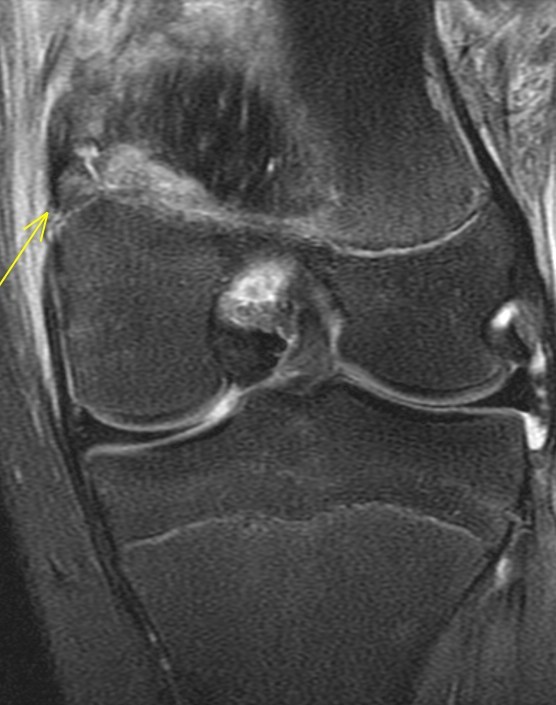

14 y/o tackled from the side after blocking a field goal in American football

The adductor magnus insertion is avulsed and there is fluid within the physis consistent with a SH injury (probable type 2 although its a bit tough to say whether the fragment was metaphyseal or epiphyseal). There was also subperiosteal blood laterally. Orthopedist saw an ossicle on plain films. Alignment good and no ACL or meniscus so he will be put in a brace and treated conservatively. Father asked if he could play in 3 weeks. I said nope.

Avulsion fracture of the adductor magnus insertion